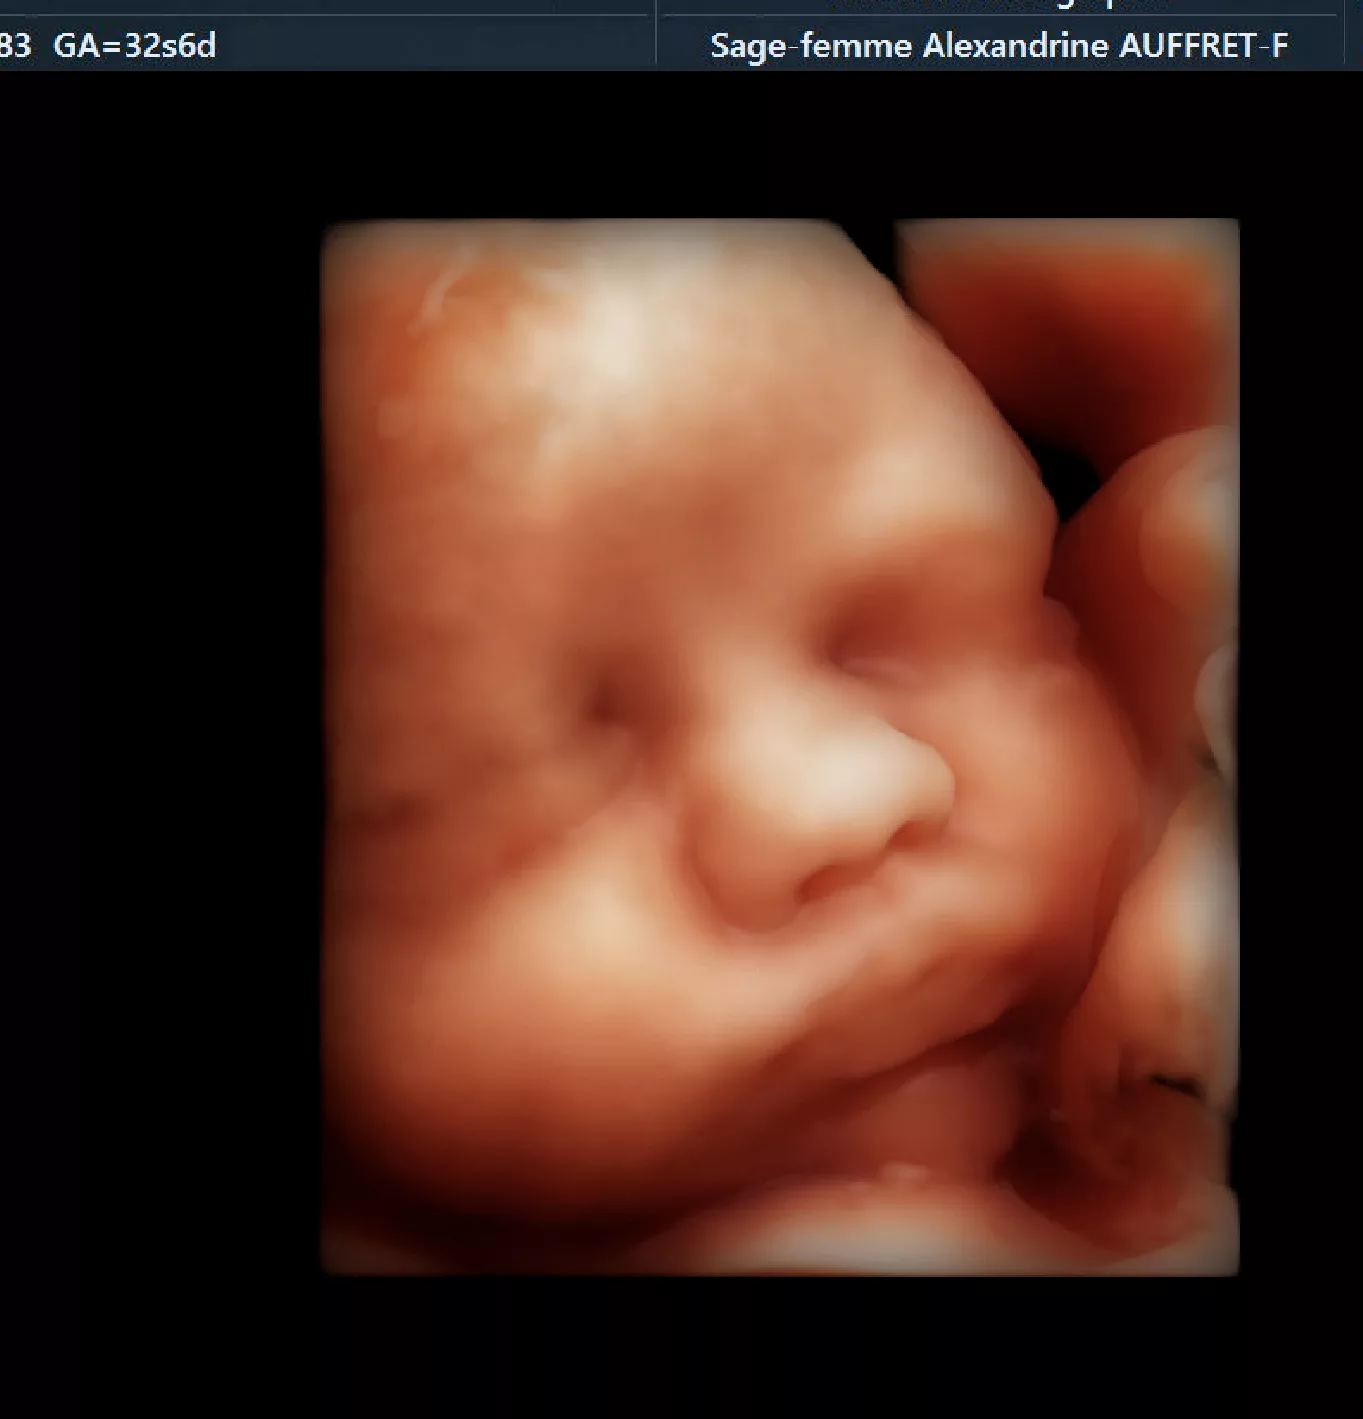

Mme Alexandrine AUFFRET-FAURE est une sage-femme échographiste. Elle pratique des échographies de dépistage aux trois trimestres de la grossesse et effectue des actes d’échographies pelviennes et gynécologiques.

Pratique de l’échographie obstétricale exclusive

Depuis 2017